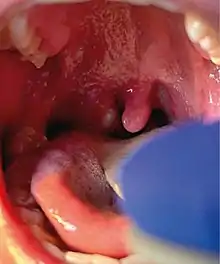

Mpox is a viral infection that manifests a week or two after exposure with fever and other non-specific symptoms, and then produces a rash with lesions that usually last for 2–4 weeks before drying up, crusting and falling off.[10] While mpox can cause large numbers of lesions, in the current outbreak, some patients experience only a single lesion in the mouth or on the genitals, making it more difficult to differentiate from other infections.[22] In infections before the current outbreak, 1–3 percent of people with known infections have died (without treatment). Cases in children and immunocompromised people are more likely to be severe.[23]